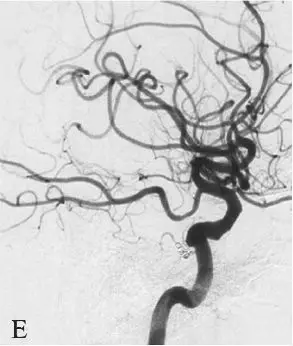

DSA:急诊全脑血管造影提示右侧颈内动脉发出变异的原始三叉动脉,该三叉动脉直接向右侧小脑前下动脉(AICA)供血区域供血,在原始三叉动脉自颈内动脉发出部位可见1枚梭形动脉瘤(图18-1B、C),右侧椎动脉发育较差,仅供血小脑后下动脉(PICA)区域(图18-1D)。右侧小脑前下动脉(AICA)未见显影,可见基底动脉发出的部分回旋支显影(图18-1E)。其余血管造影未见明显异常。

D:右侧椎动脉造影;

E:左侧椎动脉造影。

图18-1变异原始三叉动脉动脉瘤患者术前CT及DSA影像